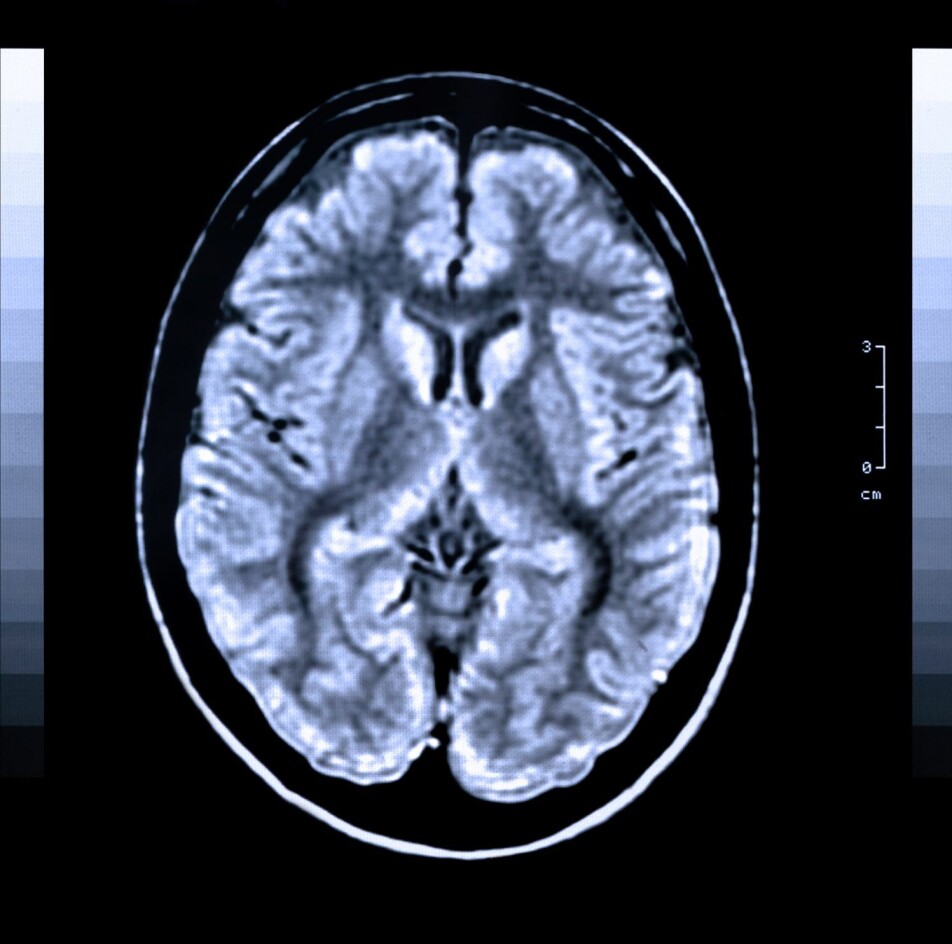

Researchers in the Nor-COAST study used MRI images of stroke patients’ brains to identify those who may develop cognitive impairment after the stroke.

The researchers examined the brains of patients who developed cognitive impairment after stroke using MRI images. MRI stands for magnetic resonance imaging, and is a method used to take pictures of the body's internal organs.

“Using MRI images of the brain, we can identify risk patients for the development of cognitive impairment after stroke with good certainty,” says the researcher.

The MRI images showed that patients who develop cognitive impairment after stroke already had brain changes prior to the stroke that may be associated with the development of cognitive impairment.

“It was mainly the case for patients with small vessel disease, who have a reduced circulation in the small blood vessels in the brain. This can lead to many small cerebral infarctions, and was associated with the development of cognitive impairment after stroke,” Schellhorn explains.

Furthermore, the results showed that the size of the stroke was associated with increased risk of developing cognitive impairment. The larger the stroke, the higher the risk of developing cognitive impairment afterwards.

There was also an association between loss of substance in the temporal lobe, which is a part of the brain associated with memory, and the development of cognitive impairment.

Eight hundred and fifteen stroke patients were included in the study. The researchers took MRI images of the brain of 410 of them.

The researchers examined these images thoroughly. On the MRI images, which were taken after the stroke, they could see which patients had changes in the brain that had been present already prior to the stroke. To do this, they used different types of MRI images, some that show that brain changes are acute and some that show brain changes of older date.

“It is a combination of specific MRI technique and interpretation that helps us say something about the age of the brain changes,” Schellhorn points out.